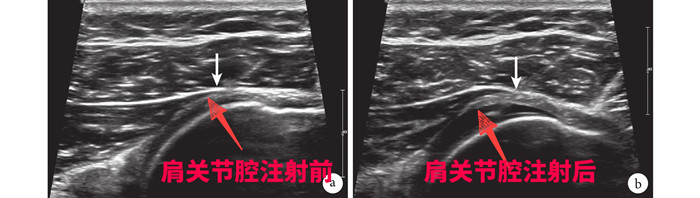

針對劉大爺?shù)那闆r,徐慧勝制定了個(gè)性化治療方案“體外沖擊波結(jié)合超聲引導(dǎo)下肩關(guān)節(jié)注射治療”,先采用沖擊波松解肩關(guān)節(jié)周圍黏連的組織,然后在超聲引導(dǎo)下將消炎鎮(zhèn)痛液準(zhǔn)確注射到肩關(guān)節(jié)腔、滑囊及神經(jīng)周圍,起到雙管齊下的作用。15分鐘后,劉大爺感覺疼痛減輕了大半,活動(dòng)明顯改善。經(jīng)過3次治療,劉大爺?shù)募缰苎滓鸦局斡?